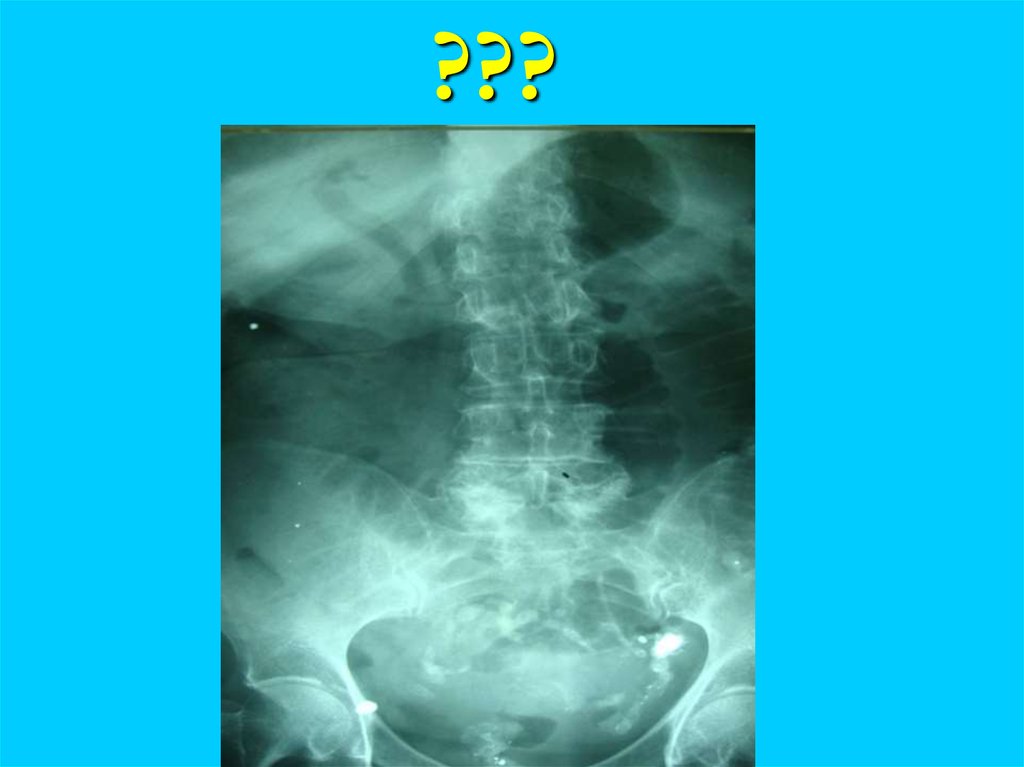

???

Рак толстой кишки